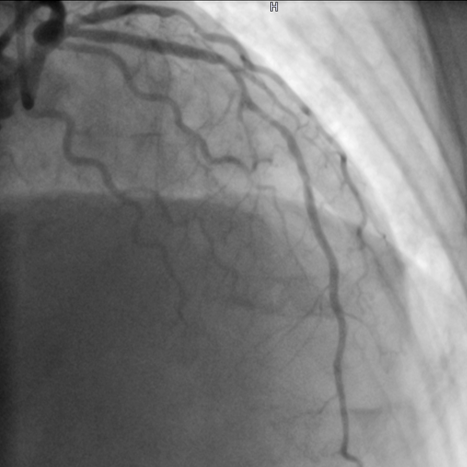

Akuter Herzinfarkt mit Verschluss des Vorderwandgefäßes (Bild 1a - Pfeil). Nach der Wiedereröffnung und dem Einsetzen einer Gefäßstütze kontrastiert sich das Gefäß wieder in ganzer Länge (Bild 1b).